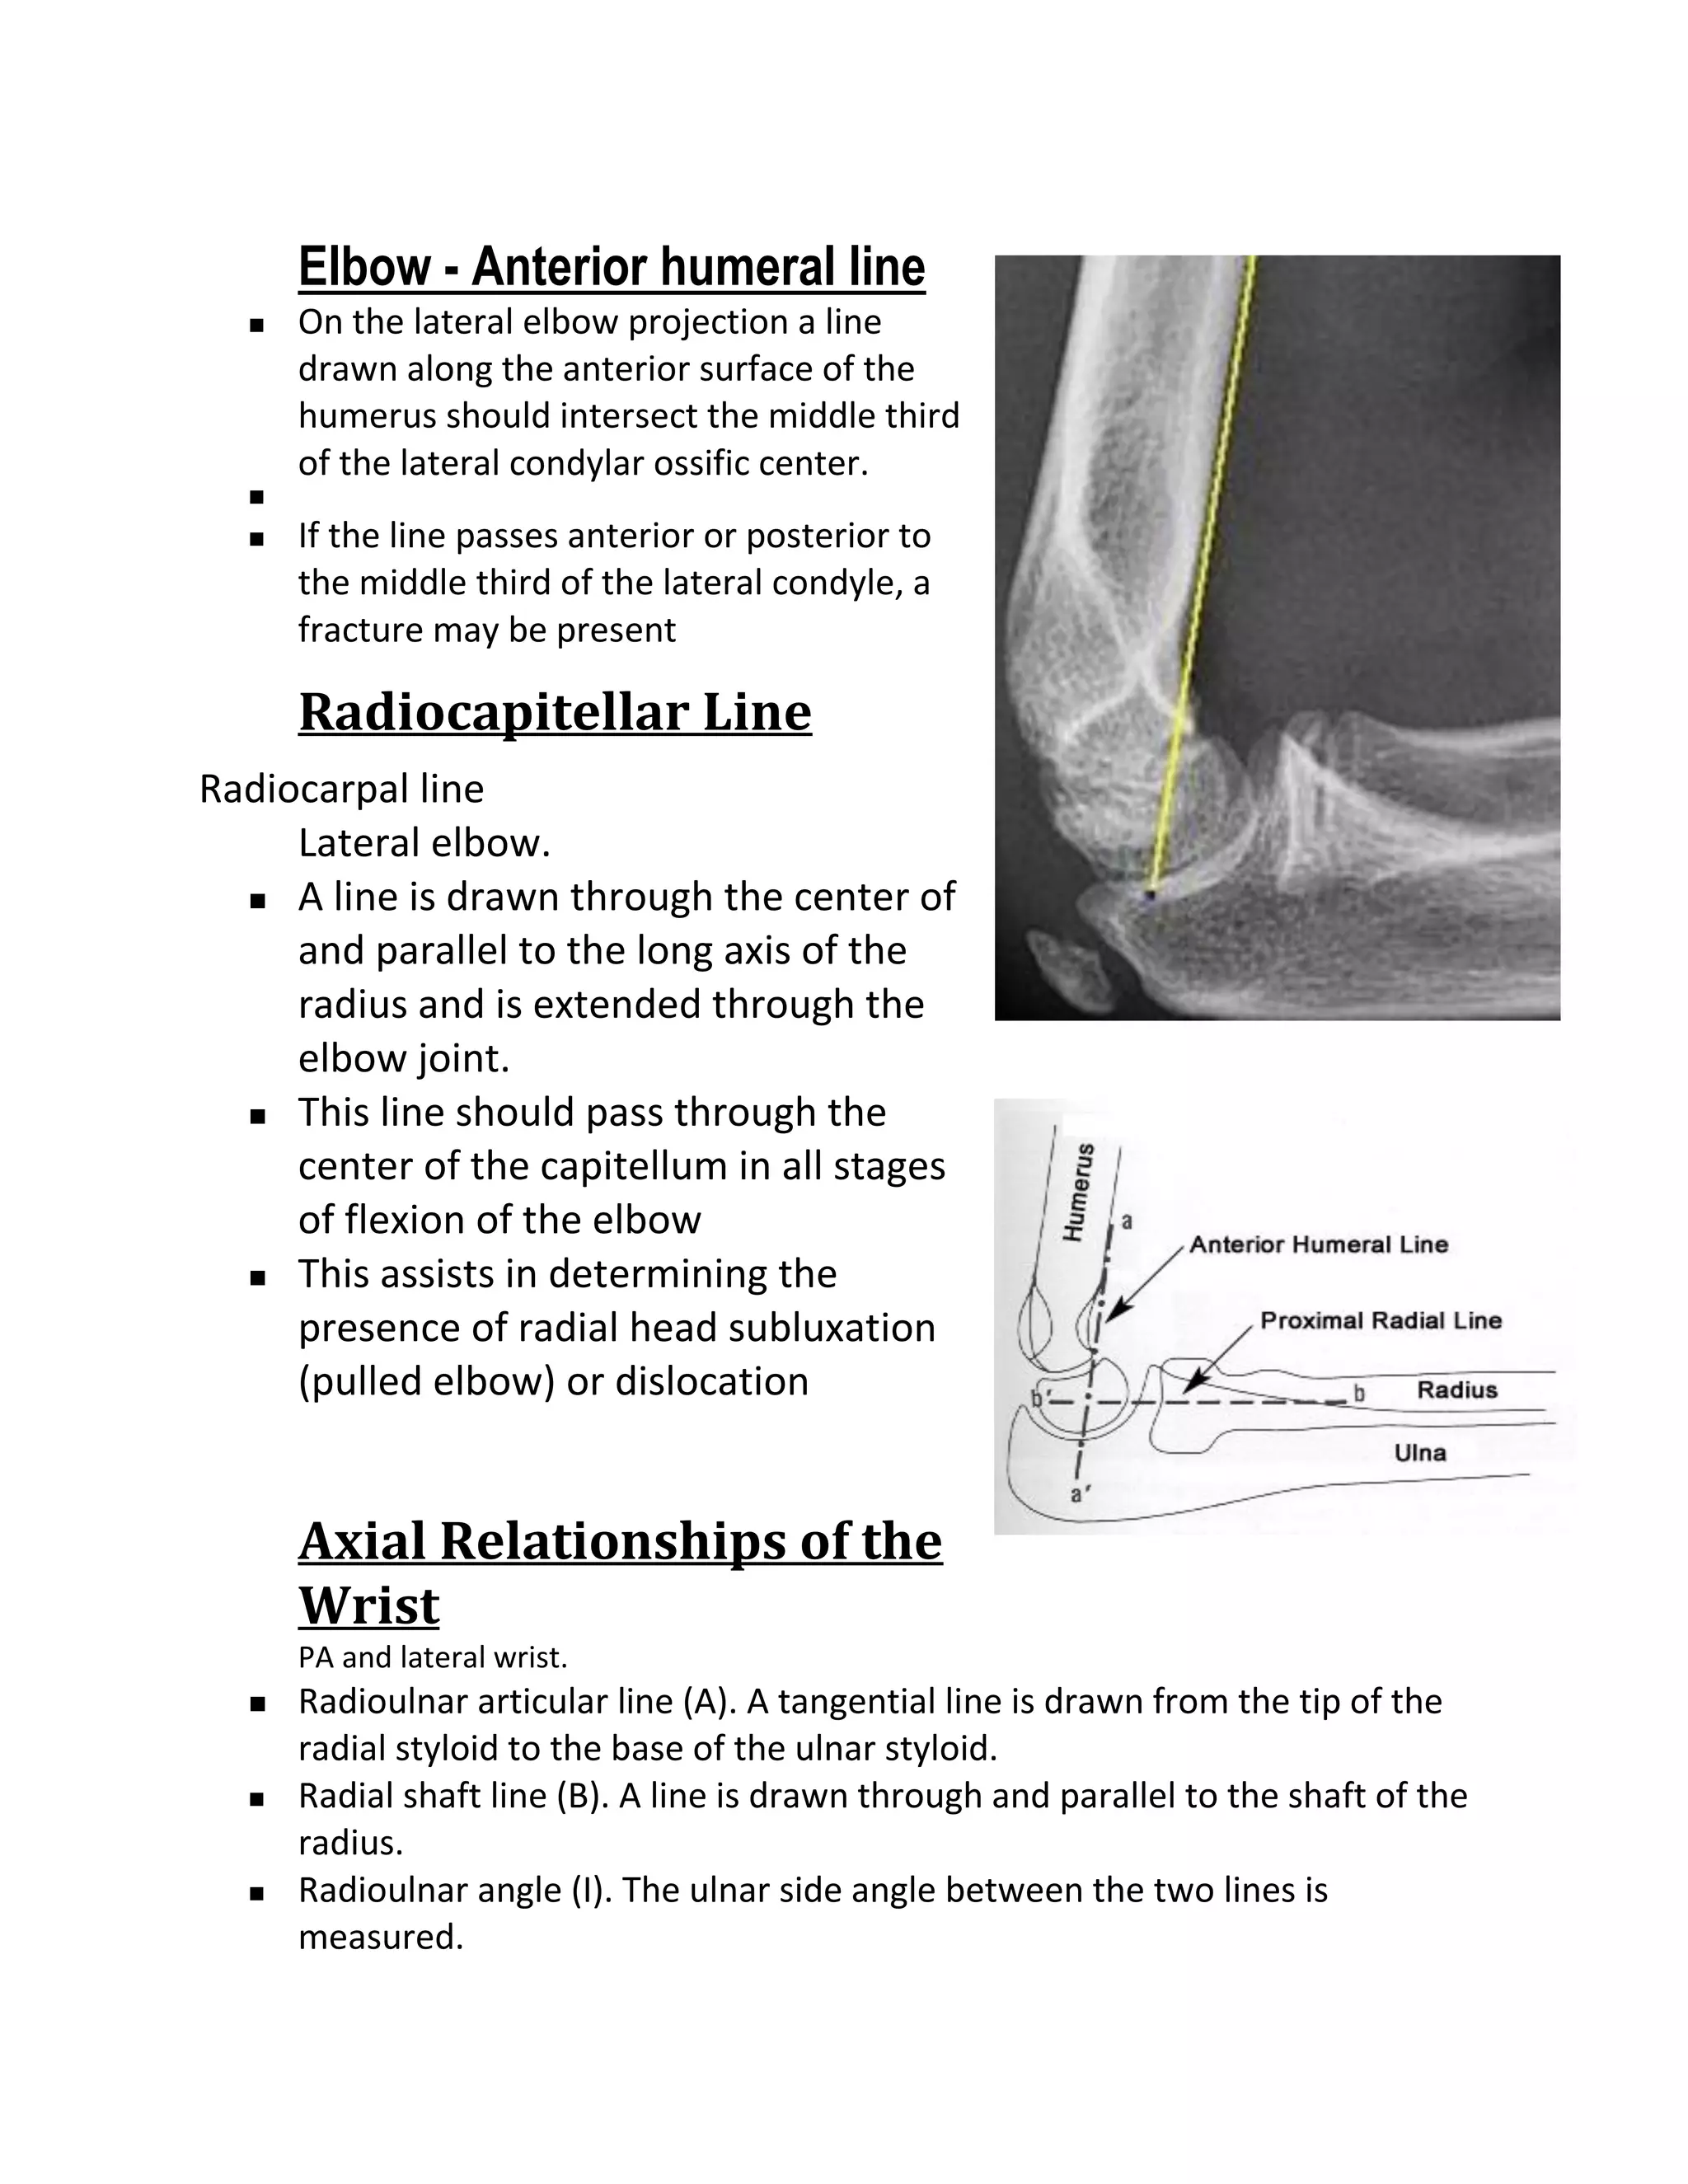

Elbow - Anterior humeral line

   On the lateral elbow projection a line

drawn along the anterior surface of the

humerus should intersect the middle third

of the lateral condylar ossific center.

   If the line passes anterior or posterior to

the middle third of the lateral condyle, a

fracture may be present

Radiocapitellar Line

Radiocarpal line

Lateral elbow.

 A line is drawn through the center of

and parallel to the long axis of the

radius and is extended through the

elbow joint.

 This line should pass through the

center of the capitellum in all stages

of flexion of the elbow

 This assists in determining the

presence of radial head subluxation

(pulled elbow) or dislocation